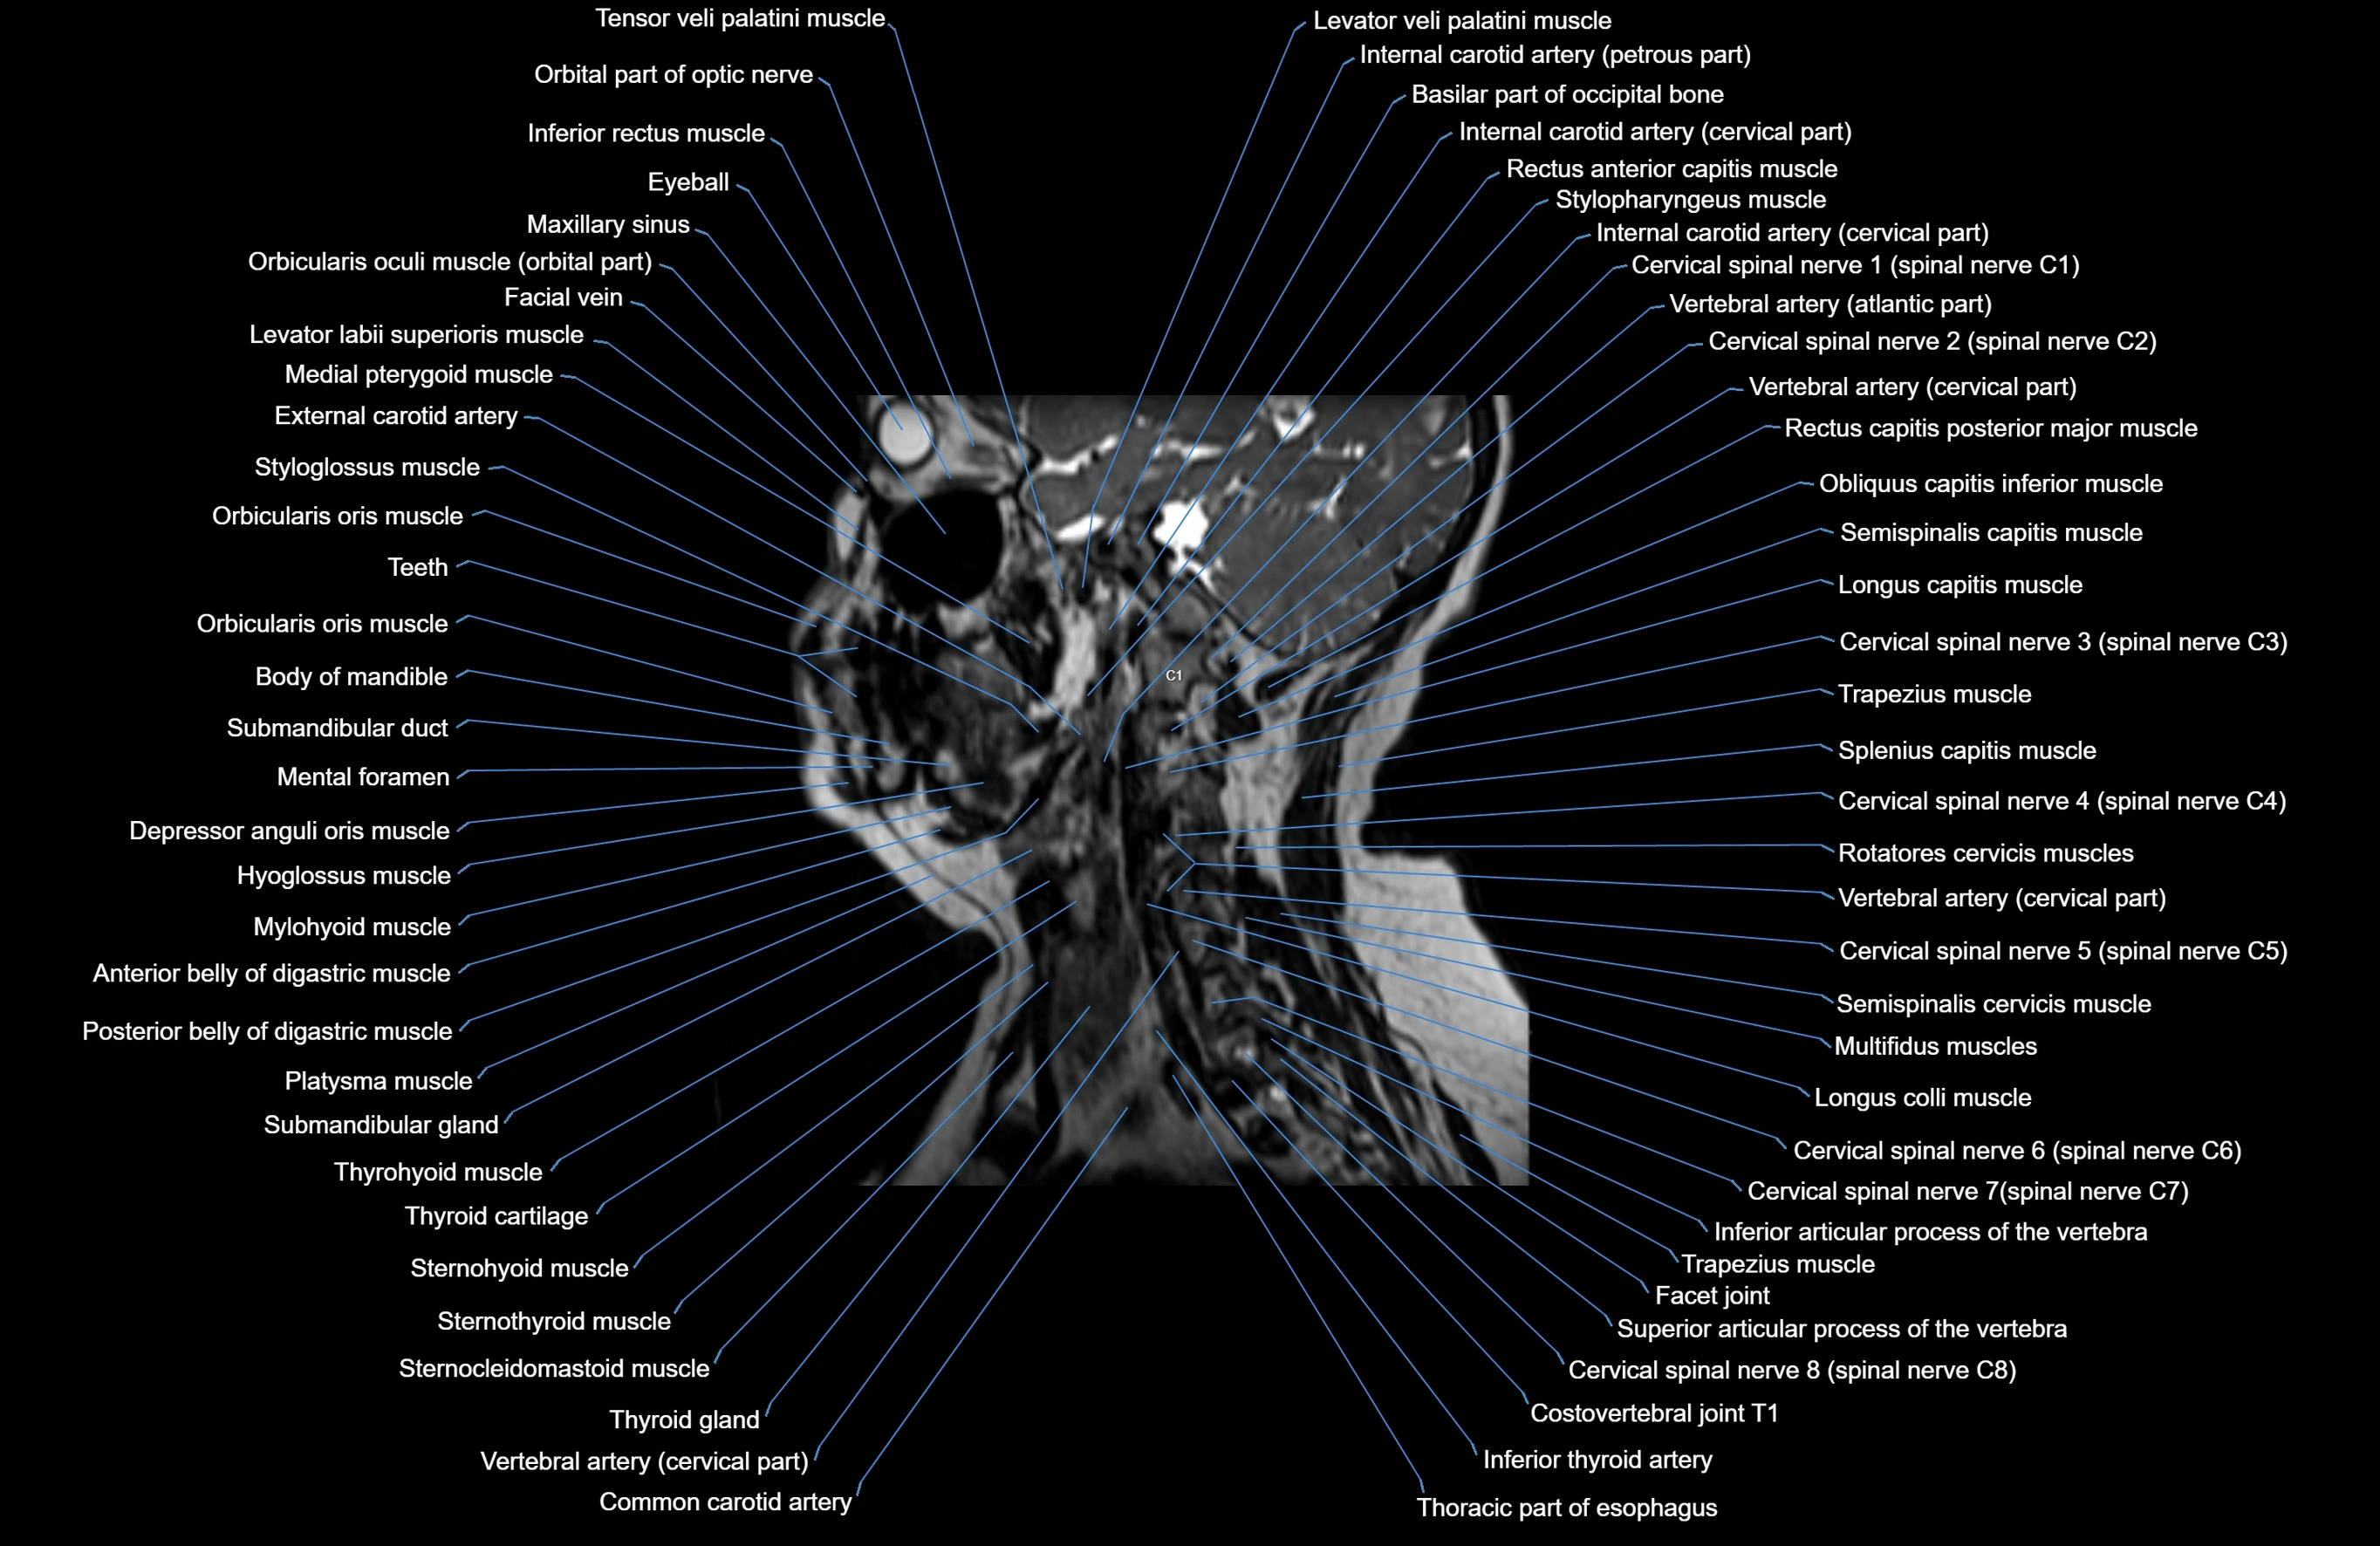

MRI images